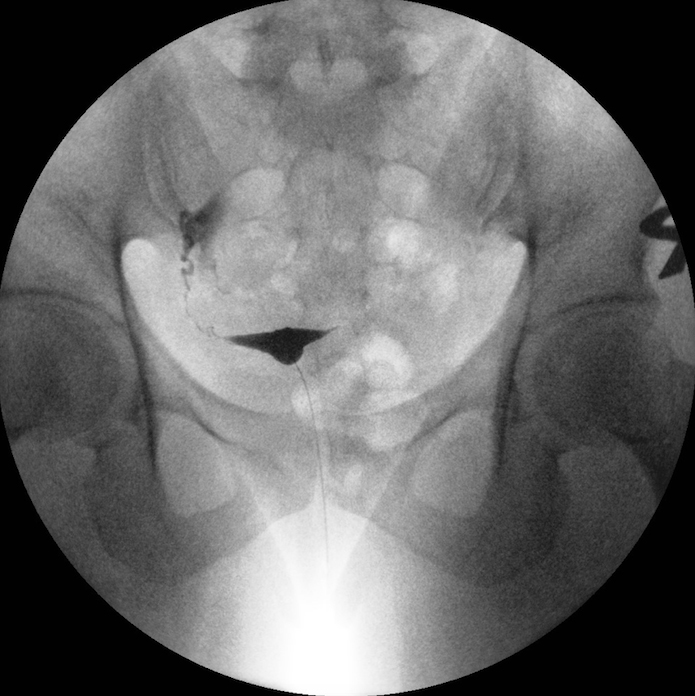

Rtg-urografija